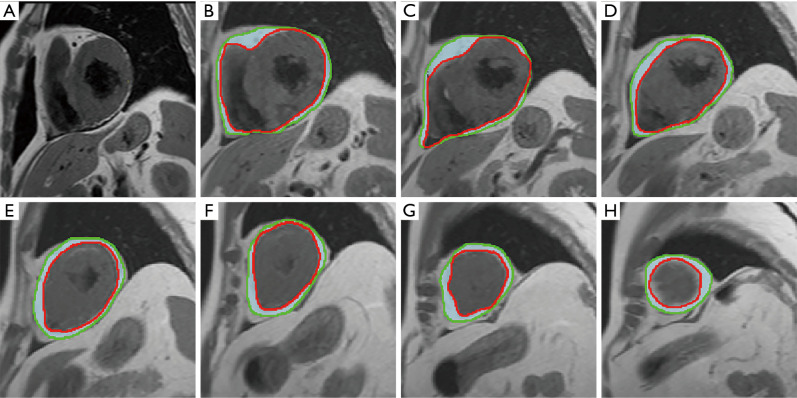

Background: In the context of acute ST-segment elevation myocardial infarction (STEMI), epicardial fat volume (EFV) has a significant impact on the formation of microvascular obstruction (MVO). This study aimed to quantitatively measure the EFV and myocardial strain parameters by cardiac magnetic resonance (CMR) and to explore their relationship with the presence or absence of mcrocirculation dysfunction after myocardial infarction.

Methods: This was a retrospective study. From June 2022 to December 2023, 56 consecutive patients diagnosed with acute STEMI who underwent percutaneous coronary intervention (PCI) were selected from The First Affiliated Hospital of Bengbu Medical University. Patients were divided into two groups based on the presence of MVO group and the non-MVO (NMVO) group, with 22 cases (39%) and 34 cases (61%) respectively. The characteristics of the infarction were assessed by delayed enhancement with gadolinium. Based on standard cine images, the global circumferential strain (GCS), global radial strain (GRS), and global longitudinal strain (GLS) of the left and right ventricles were evaluated using CMR feature tracking (CMR-FT) imaging. The volume of EFV was quantified along the short-axis slices of the left and right ventricles at the end of diastole by CMR imaging. The differences in baseline characteristics, EFV, and myocardial strain parameters between the groups were compared using Pearson or Spearman correlation analysis. The specificity and sensitivity of myocardial strain parameters in predicting MVO were obtained using receiver operating characteristic (ROC) curves. The predictive factors for MVO were analyzed using univariate and multivariate logistic regression analyses.